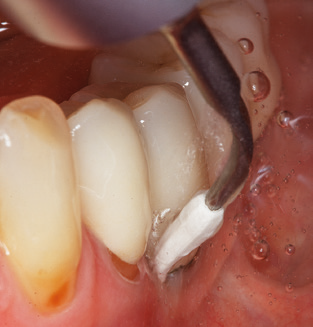

Fig. 4: Flexible probes with millimetre markings are recommended for the probing of dental implants (e.g. Colorvue Kit PCV11KIT6, Hu­Friedy). – Fig. 5a and b: A straight working tip (1P, W&H Dentalwerk Bürmoos GmbH) is a suitable instrument for use on all natural teeth. – Fig. 6: Curved working tips (3Pr/3Pl, W&H Dentalwerk Bürmoos GmbH) lend themselves to the processing of difficult-to-reach areas of the tooth and root surfaces (e.g. furcations). – Fig. 7: The tapered, hexagonal implant cleaning tip (1I, W&H Dentalwerk Bürmoos GmbH) permits atraumatic and efficient cleaning of the crown and abutment surfaces. – Fig. 8: Titanium and carbon curettes are suitable instruments for the manual cleaning of the implant surfaces.

Of course, working tips for the cleaning of implant surfaces are also indispensable for SPT in patients fitted with implants. The implant cleaning attachment on the system used here is characterised by its tapered, hexagonal design. This design allows light, atraumatic penetration of the peri-implant pocket and displays a good cleaning performance (Fig. 7).